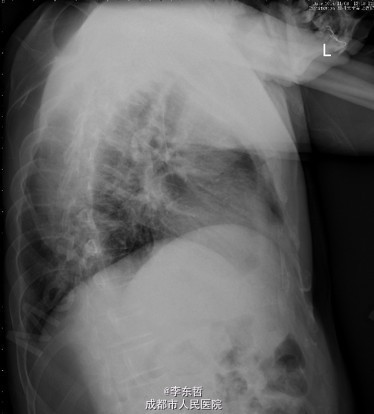

患者男,62岁,因“双髋疼痛4年,加重伴活动受限1年”入院。病员诉入院前4年无明显诱因出现双侧髋部疼痛,行走后疼痛加重,疼痛能忍受,双侧髋部无红肿,皮温不高,无畏寒、发热,休息后疼痛能自行缓解,无夜间疼痛,在当地医院行止痛药内服、理疗治疗,疼痛稍缓解。逐渐加重,1年前双侧髋部疼痛、跛行明显加重,左髋活动受限,行走困难,给予对症治疗症状无明显改善,遂到我科门诊就诊,X线片提示:双侧股骨头坏死,建议手术治疗,故于今日以“双侧侧股骨头坏死”收入我科进一步治疗。

查体:生命体征平稳,心肺腹未见异常;跛行,双左下肢较右下肢短缩1cm,左、右腹股沟中点深压痛,左、右髋叩击痛,左髋屈20°,伸0°,外展10°,内收10°,右髋屈60°,伸0°,外展20°,内收20°。双髋内、外旋活动受限,诱发疼痛,左侧重。 辅助检查:x线片示双侧股骨头坏死、塌陷变形,左侧明显,左髋半脱位。

初步诊断:1、左侧股骨头坏死伴内收肌挛缩(Ficat IV期);2、右侧股骨头坏死(Ficat IV期);3、右膝骨关节炎伴外翻畸形;入院后积极完善术前检查及准备,择期行手术治疗。